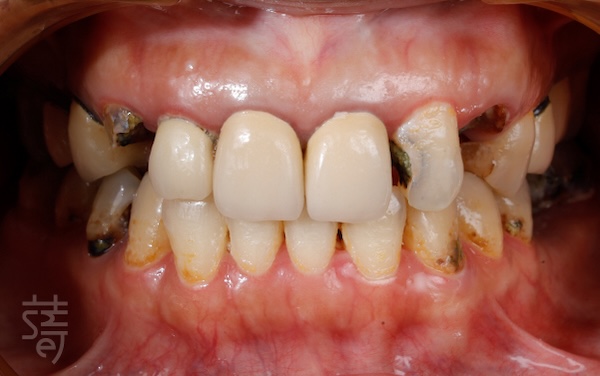

像許多曾被看牙經驗嚇到的病患一樣,陳太太長年對牙科懷有深深恐懼。牙齒出問題時,她總是一拖再拖,直到疼痛難忍才走進診間。當她來到蒔美牙醫諮詢全口植牙重建時,口腔狀況已相當複雜:多顆缺牙、大範圍蛀牙、根尖發炎、牙齒斷裂與舊假牙不密合,疼痛成了生活的一部分,吃飯也變得困難。更讓她難受的是笑容的流失,不再敢自在開口說話。

Like many patients who have been traumatized by dental experiences, Mrs. Chen had lived with a deep fear of the dentist for years. Every time a tooth caused pain, she would put off treatment until it became unbearable. When she finally came to Smile Dental for a consultation about full-mouth reconstruction, her oral condition was quite complex: multiple missing teeth, widespread cavities, root inflammation, fractured teeth, and ill-fitting old crowns. Pain had become a daily burden, and eating was a constant struggle. Even more disheartening, she had lost the confidence to smile freely or speak without hesitation.

美觀臨時假牙:陪伴每個階段

Temporary Esthetic Dentures: Supporting Every Stage of Full-Mouth Reconstruction

植牙期間,蒔美設計美觀臨時假牙,讓療程中不需經歷「空窗期」。 臨時假牙保持自然外觀,也能順暢進食與說話。隨著骨頭癒合與咬合穩定,醫師微調假牙位置與高度,確保正式假牙完成時,功能與美觀達到理想平衡。

During the full-mouth implant process, Smile provides patients with temporary esthetic dentures, ensuring there’s no “gap” in appearance or function.These temporary dentures maintain a natural look while allowing patients to eat and speak comfortably.As the bone heals and bite stabilizes, doctors make fine adjustments to ensure the final permanent teeth achieve both optimal function and aesthetics.